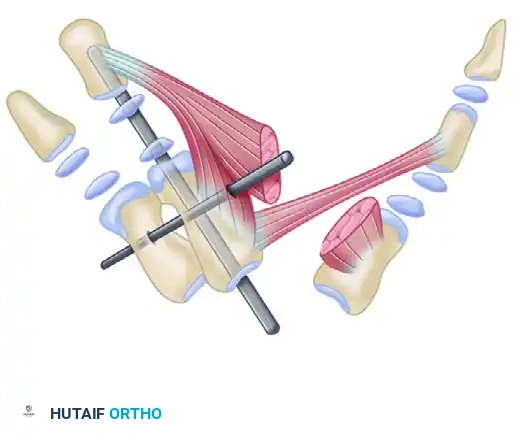

Biomechanics of the Triceps Transfer

The biomechanical objective of the Menelaus procedure is to reroute the triceps tendon anterior to the axis of elbow rotation, thereby converting its moment arm from extension to flexion. By securing the transfer to the coronoid process of the ulna, the surgeon recreates a near-anatomic insertion site for the brachialis, optimizing the mechanical advantage and excursion of the transferred muscle-tendon unit.

Step 3: Tendon Routing and Fixation

* Tubularize (roll) the periosteal tongue and the distal triceps tendon using a running locking suture (e.g., #1 or #2 nonabsorbable braided suture) to create a strong, cylindrical graft.

* Identify the coronoid process of the ulna anteriorly. Using a drill and curettes, create a transosseous tunnel through the coronoid process.

* Pass the tubularized triceps tendon through the coronoid tunnel from anterior to posterior.

Step 4: Tensioning and Closure

* With the elbow held in 120 degrees of flexion and the forearm in neutral rotation, apply maximum physiological tension to the transferred tendon.

* Secure the transfer to the ulna using heavy nonabsorbable sutures, tying them over a bony bridge or utilizing a biotenodesis screw if bone stock permits.